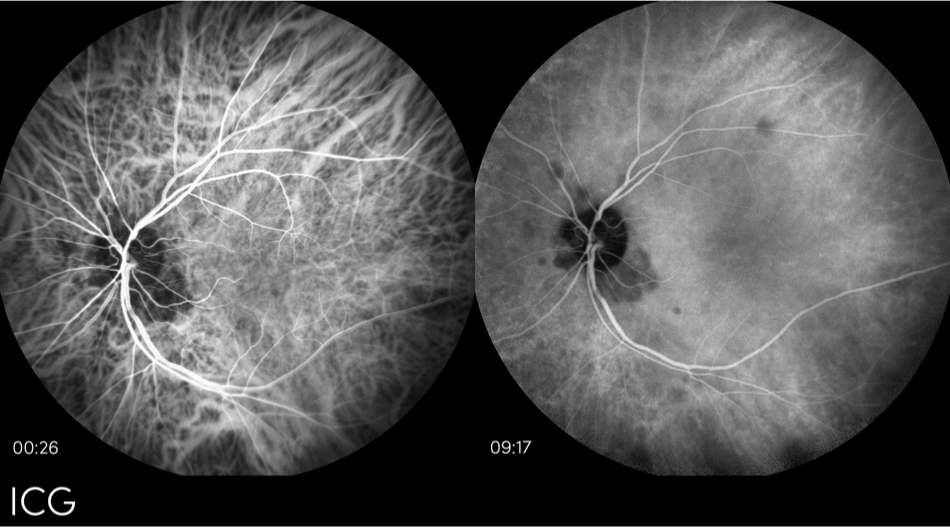

Angiografía con verde de indocianina (AVIC)

La ICG es una técnica de imagen utilizada para excluir la DMAE húmeda y también para evaluar las lesiones atróficas en la retina de la DMAE seca.13 El concepto de AVIC es como la autofluorescencia del fondo de ojo. También utiliza la luz que se inyecta en la retina para excitar la fluorescencia, aunque la AVIC utiliza un tinte inyectable en el torrente sanguíneo y permite una mejor resolución de la imagen.13